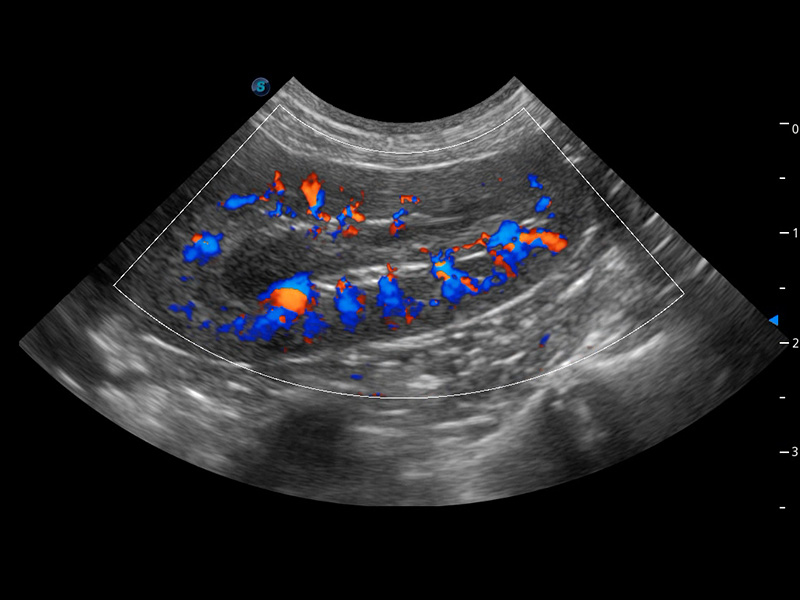

ProPet 60 作为一款高端台式动物超声设备,为动物医生的日常诊断提供了一系列贴合动物临床需求、解决临床实际问题的高级成像功能。凭借全系列高清探头,满足医生对腹部、心脏、生殖、浅表、肌骨等成像的所有需求,切实帮助您提升检查效率,提高诊断信心。

动物是人类最亲密的朋友和最值得信赖的伙伴。玖鼎集团也一直致力于探索动物专用的超声影像解决方案。 全新推出的ProPet系列,是玖鼎集团在动物超声影像智能化、专业化、精准化的一次跨越式革新。动物不能用言语来表述自己的不适,通过超声影像,ProPet系列搭建了动物医生与不同物种沟通的“桥梁”,为动物医生注入了“治愈之力”。